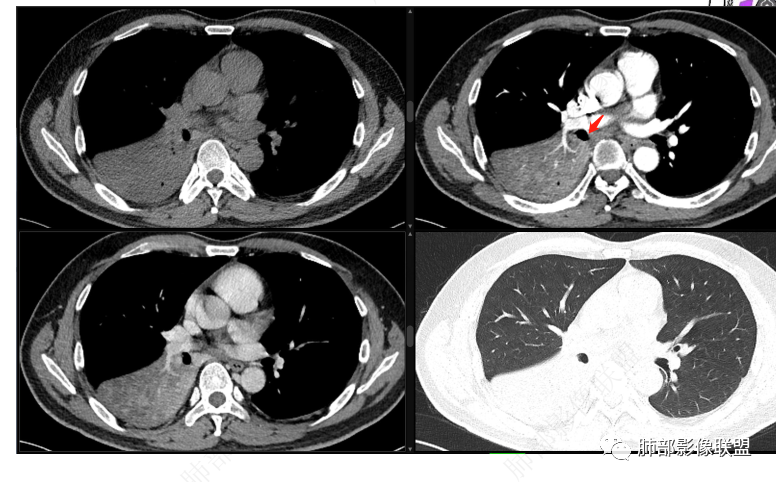

中央型肿瘤pk周围型肿瘤  。壮年男性,热咳一周伴气喘,中性白细胞升高,临床是个感染过程。支持中央型病变的证据:1  肺门明显强化结节 2 横s征  3 支气管粘液栓  4 主支气管变窄,似见冰山征      支持周围型病变:1 按叶段塑形  2 血管造影征  3 病灶内弥漫高强化  4 周围伴磨玻璃灶,但境界不清继发感染?误吸?综合 中央型肿瘤可能大:类癌》鳞癌

中间段支气管

基底干是外侧朝腔内压迫?还是外侧壁占位突入腔内?

这是肺门淋巴结压迫、侵犯支气管导致堵塞?还是腔内本身肿瘤?

远端支气管是粘液栓

这个问题关系到诊断的问题

首先血管未见明显侵犯、移位,提示病灶:炎性;肿瘤:外朝内——含粘液类腺癌(肺门淋巴结转移),腔内肿瘤(鳞癌、腺癌、类癌、小细胞、粘液表皮等)

腔内肿瘤,远端堵塞

如果重建确定在腔内,那就鉴别黏表

我觉得粘液表皮可能要放前面

腔内